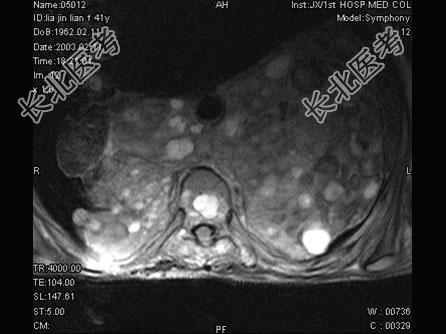

- 单项选择题女,41岁, 胸背部疼痛,肢体活动感觉障碍2年余, MRI检查见T

、T

椎体及附件骨质破坏,并向周围形成巨大肿块影, 呈T1低信号为主,T2加权有多个大小不一圆形混杂高信号, 边界清楚,最可能的诊断是 ( )